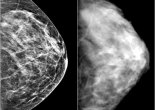

CLICK to save a life

it’s a proven fact that early detection of breast cancer saves lives. and what’s one of the best ways to prevent and diagnose breast cancer in its early stages? >>> … Continue reading